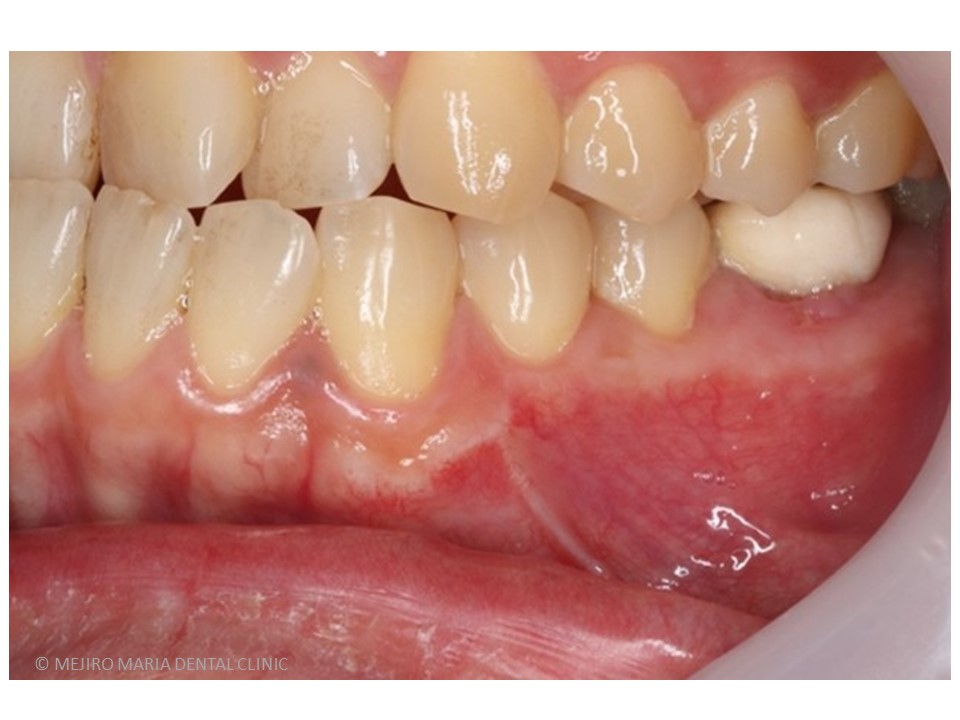

治療後の様子

歯根端切除術を施した後にはサイナストラクト(瘻孔・フィステル)の消失が確認でき、根尖性歯周炎は寛解へ向かっていると考えられます。

今後、最終補綴処置を行い最低2年のフォローアップ(経過観察)を行い、レントゲンで注意深く根尖周囲組織の治癒を確認していきます。